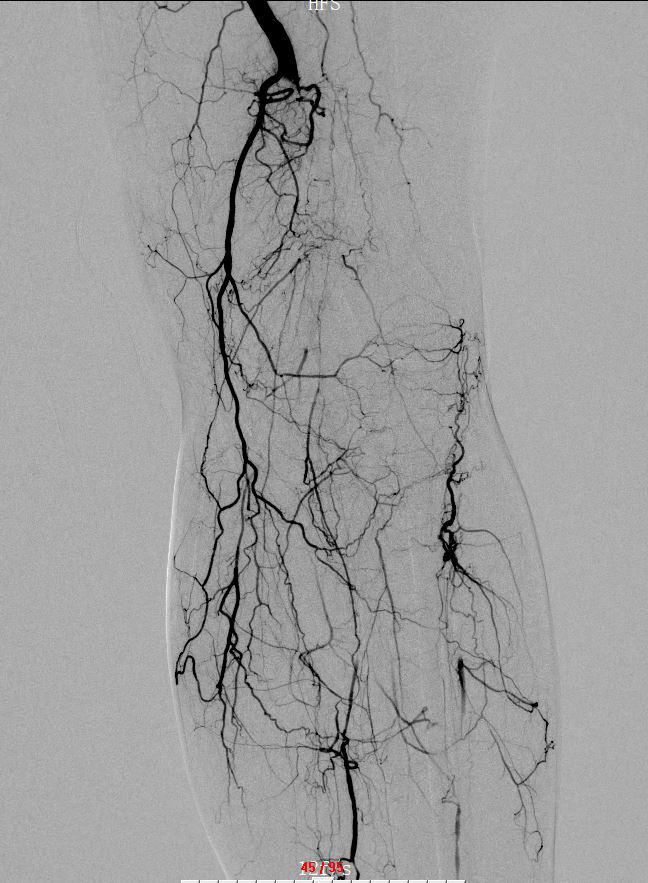

出院后,龙林主任指导团队为患者实施慢诊左下肢制影,左下肢浅动脉下段 + 腘动脉与栓、留置导管溶栓术,抽掏出 3~4 条蚯蚓大小的血栓。术后,患者下肢痛苦悲伤的情况明显好转。

" 招致他下肢动脉突收血栓的原因是房颤 ",龙林表示,房颤患者因为心净不克不及纪律跳动,所以随便构成血栓。为完全打点李嗲嗲的病症,龙林主任指导团队于 6 月 4 日再次为他实施左下肢动脉制影 + 左下肢动脉球囊扩大术,仅用一根 2.5 × 120mm 少的球囊导管便成功打通梗塞的血管。脚术耗时约 1.5 小时,术中几乎无出血,仅留下针眼大小的脚术创伤。

术后,白叟左下肢动脉血流光复畅达,皮肤冰冷的情况也明显好转,于 6 月 8 日顺利出院。